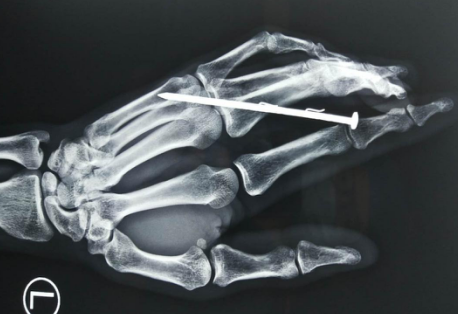

近日,在徐州某工地干活的王师傅在使用气钉枪往墙上钉钉子时,操作失误,一根钢钉不偏不倚地射进王师傅的手掌,气钉枪强大的冲击力让钢钉瞬间贯穿了王师傅的中指指骨。意外发生后,王师傅的工友第一时间带着王师傅来到betway在线登陆手外科就诊。

接诊的手外科唐洪伟医生在看完患者的ct后发现,铁钉对患者的指骨、血管和肌腱都造成了一定的损伤,同时由于铁钉上还有两根倒刺,这根“带刺的玫瑰”也为手术增加不少难度。

经过诊断后,唐医生为患者实施了异物取出手术。由于伤口较小,铁钉上又有倒刺,为了避免铁钉上的倒刺折断在手掌内,造成二次损伤,在手术过程中用到了显微镜进行辅助。同时为防止铁钉上的铁锈感染伤口,唐医生还为其进行了伤口彻底清创。经过几个小时的紧张手术,钢钉被完整取出。目前,患者恢复良好。唐医生表示,被铁钉贯穿致伤是非常危险的,幸好伤者送院及时,经过紧急救治,手指恢复良好。